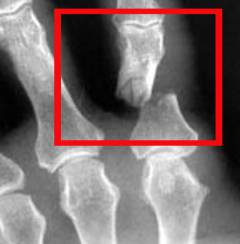

Переломы пальцев делятся на открытые и закрытые. Закрытый перелом характеризуется целостностью кожи, а открытый — повреждением кожи острыми осколками кости. Фаланги, будучи трубчатыми костями, редко образуют острые концы при переломе, что связано с их небольшими размерами и прочностью кожи. Открытые переломы повышают риск осложнений, таких как остеомиелит — воспаление костного мозга.

Закрытые и открытые переломы фаланг подразделяются на переломы со смещением и без него. Переломы со смещением делятся на переломы с расхождением и захождением краев костных отломков.

Диагностика основана на клинических признаках и подтверждается рентгенографией кисти или пальца в двух проекциях, что позволяет уточнить локализацию и характер перелома. Хотя компьютерная томография теоретически возможна, на практике используется редко из-за высокой стоимости и достаточности рентгена.

Рентгенографию следует повторить после снятия гипса для контроля сращения кости и положения фиксационных устройств.

Диагностика перелома пальца основывается на клинических признаках. Для подтверждения диагноза проводят рентгенографию кисти или конкретного пальца в прямой и боковой проекциях. Этот метод позволяет выявить перелом, уточнить его локализацию, форму и степень тяжести, что важно для выбора метода лечения.

Хотя возможны более современные методы, такие как компьютерная томография, на практике они используются редко. Причины — высокая стоимость и то, что рентгенография в двух проекциях обычно предоставляет достаточную информацию для понимания характера перелома и выбора лечения.

Рентгенографию пальца следует повторить после снятия гипса для контроля качества сращения кости и правильности расположения фиксационных устройств.